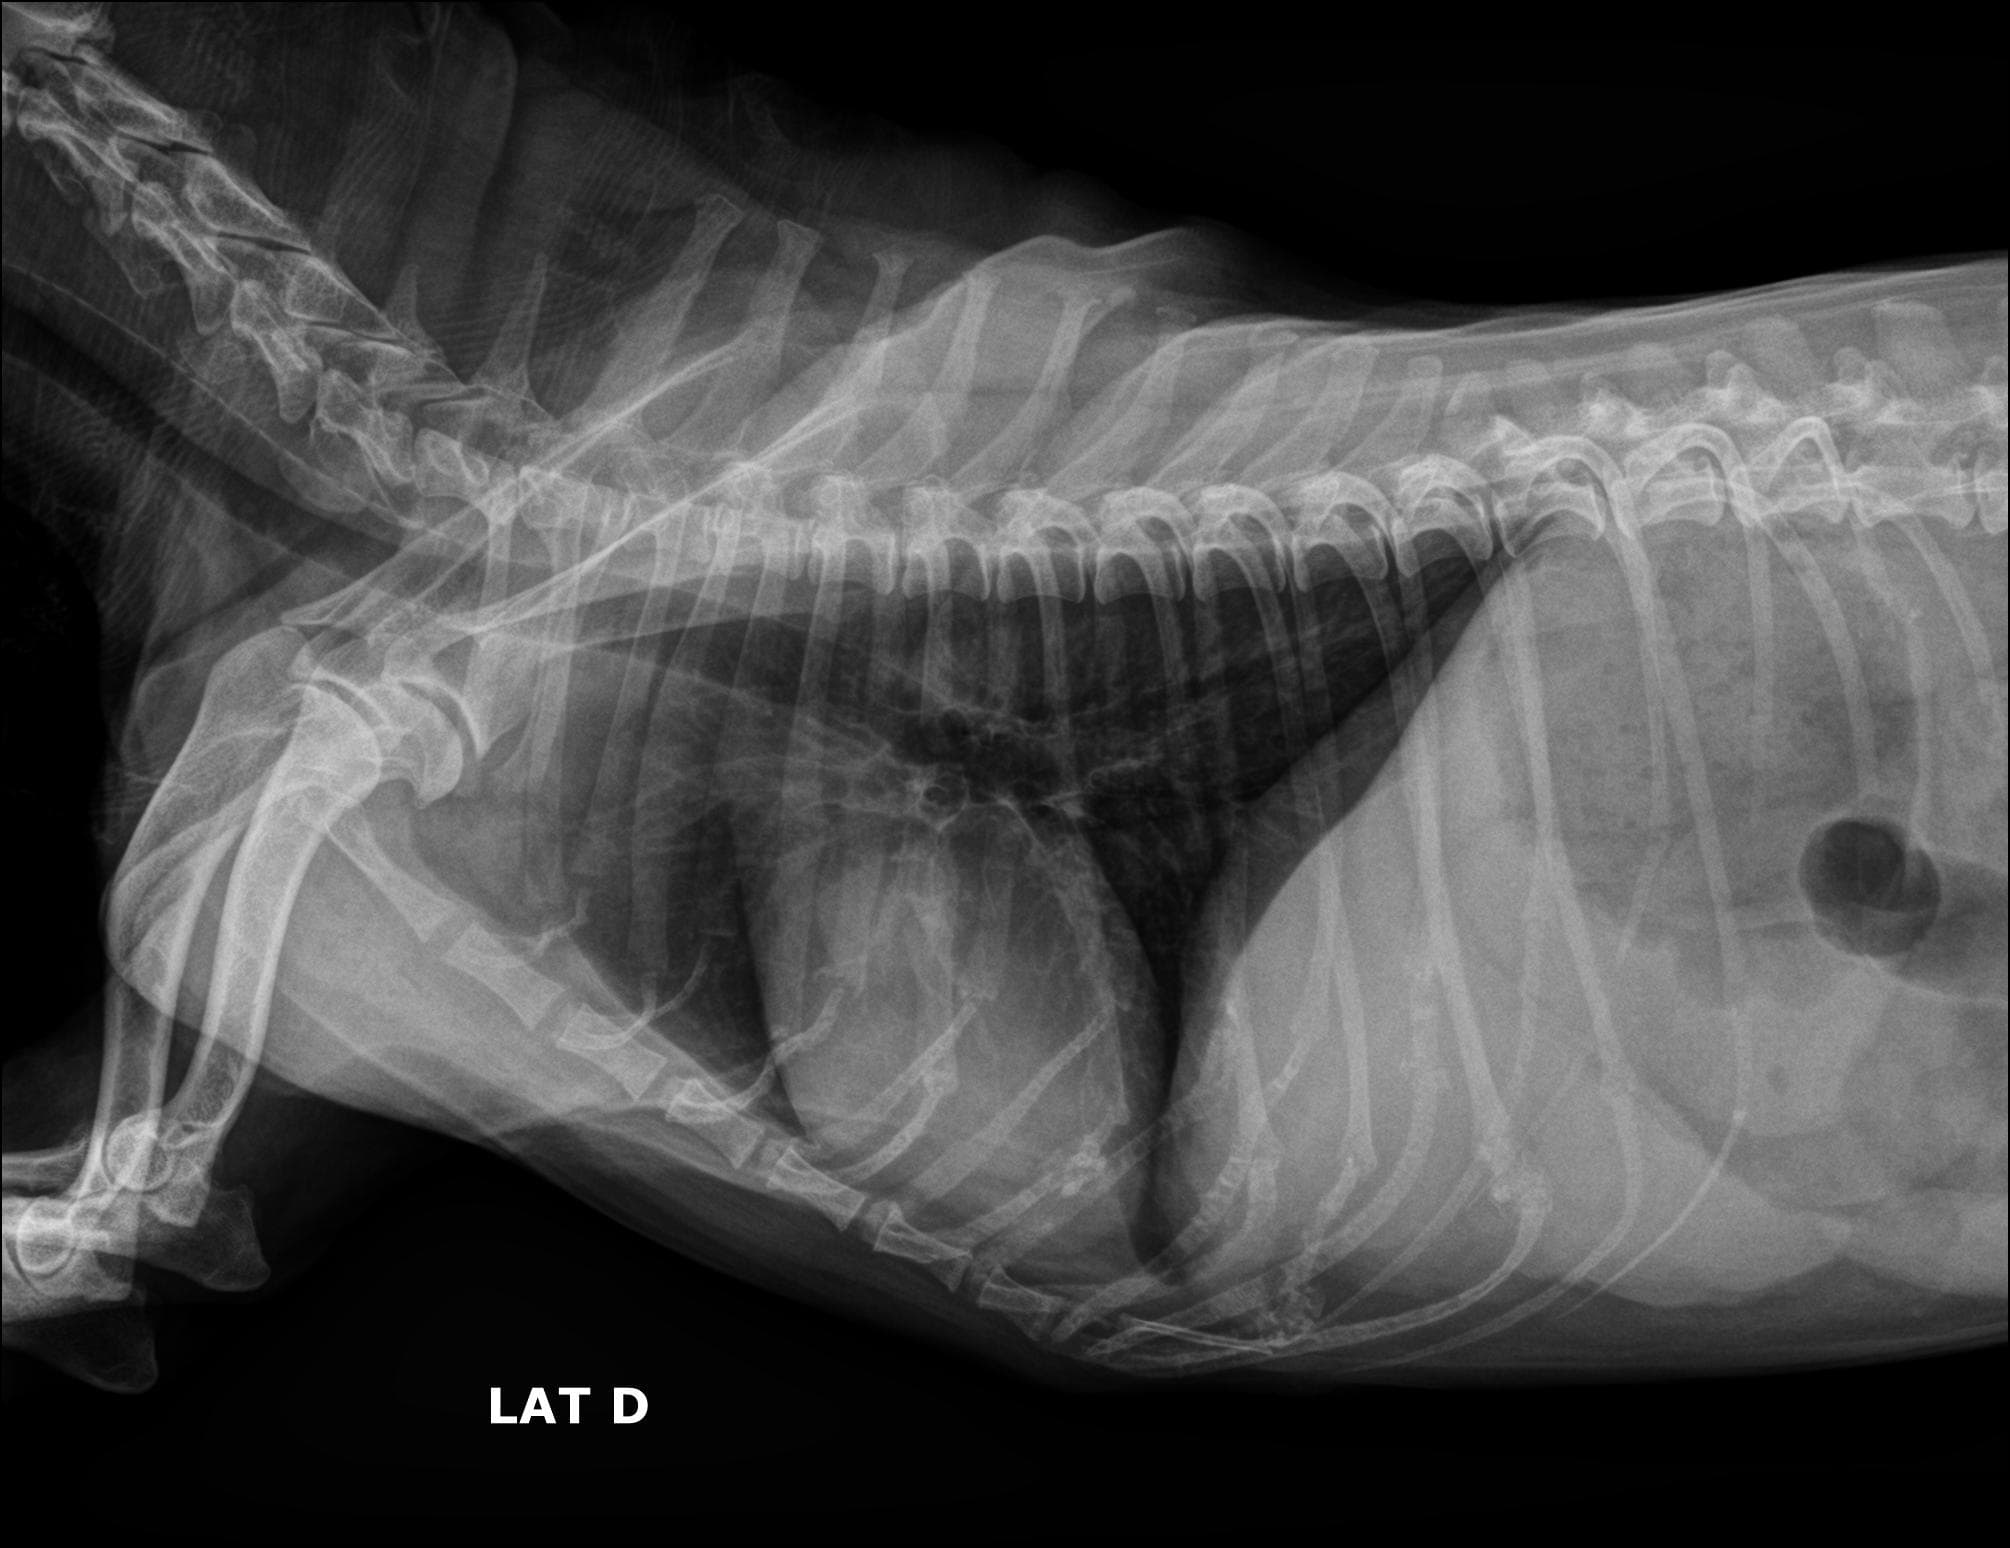

Nosso serviço de radiologia digital é projetado para oferecer diagnósticos precisos para cuidar da saúde dos pets. Contamos com equipamentos de última geração que nos permitem capturar imagens de alta qualidade e definição, fornecendo uma visão clara das estruturas. Essa tecnologia avançada nos permite identificar diversas condições médicas com maior precisão e detalhamento.